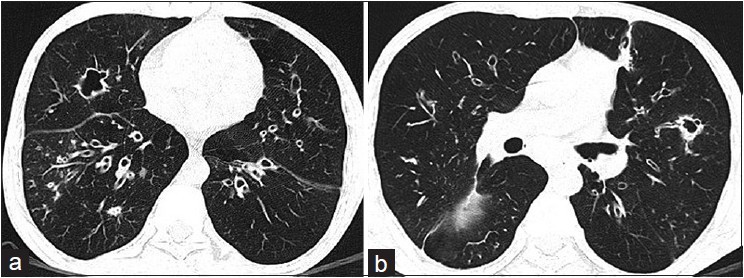

Bronchiectasis Etx

[Poor mucociliary clearance] –> Bacterial infection –> Inflammation –> Bronchial Dilation and thickening–> [tenacious productive cough w/ hemopytsis]

Dx = High Res CT Chest

Gold standard dx for Bronchiectasis

High Res CT chest scan (initial dx)